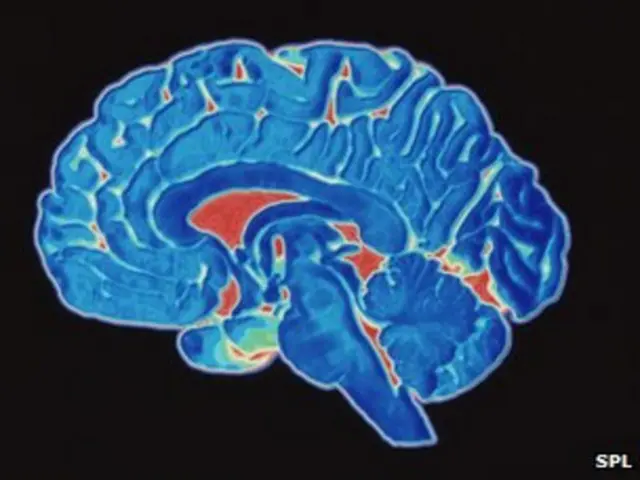

Sammuun kutaa qaamaa ulfaatinaan isa xiqqaa ta’e- kiilogiraama 1.5 qofa ta’e (ulfaatina qaamaa keessaa giddugaleessaan dhibeentaa 2 qofa kan qooddatu) ta’ee, garuu anniisaa guutummaa qaamaa keessaa harka 20 kan fayyadamuudha. Qaama keessaa kan akka sammuu anniisaa guddaa fayyadamu hin jiru.

Niwuroonota biiliyoona 100 ta’an irraa kan ijaarame sammuun, ulfaatina xiqqaa qabaatus garuu sochii fi haalaa fi amala hunda kan to’atuudha.

Sammuun anniisaa waatii 23 maddisiisuu danda’a

Sammuun anniisaa waatii 23 kan ampuulii tokko bareechee ibsuu danda’u qaba. Humni kun argamuuf boqonnaa ga’aa barbaada.

Sammuun niwuroonota biiliyoona 100 ta’an of keessaa qaba, niwuroononni kunneen wal quunnamtii tiriiliyonaa 1,000 ta’u uumuun tajaajila qaamaaf kennu. Yeroo keessa qindaa’anii qabiyyee fi dandeettii sammuu kan guddisan niuroonota kunneeni.

Tishuun sammuu hamma cirrachaa geessu tokkittiin niwuroonota kuma 100 fi iddoowwan niwuroononni itti walquunnaman (synapses) biliyoona qabdi.